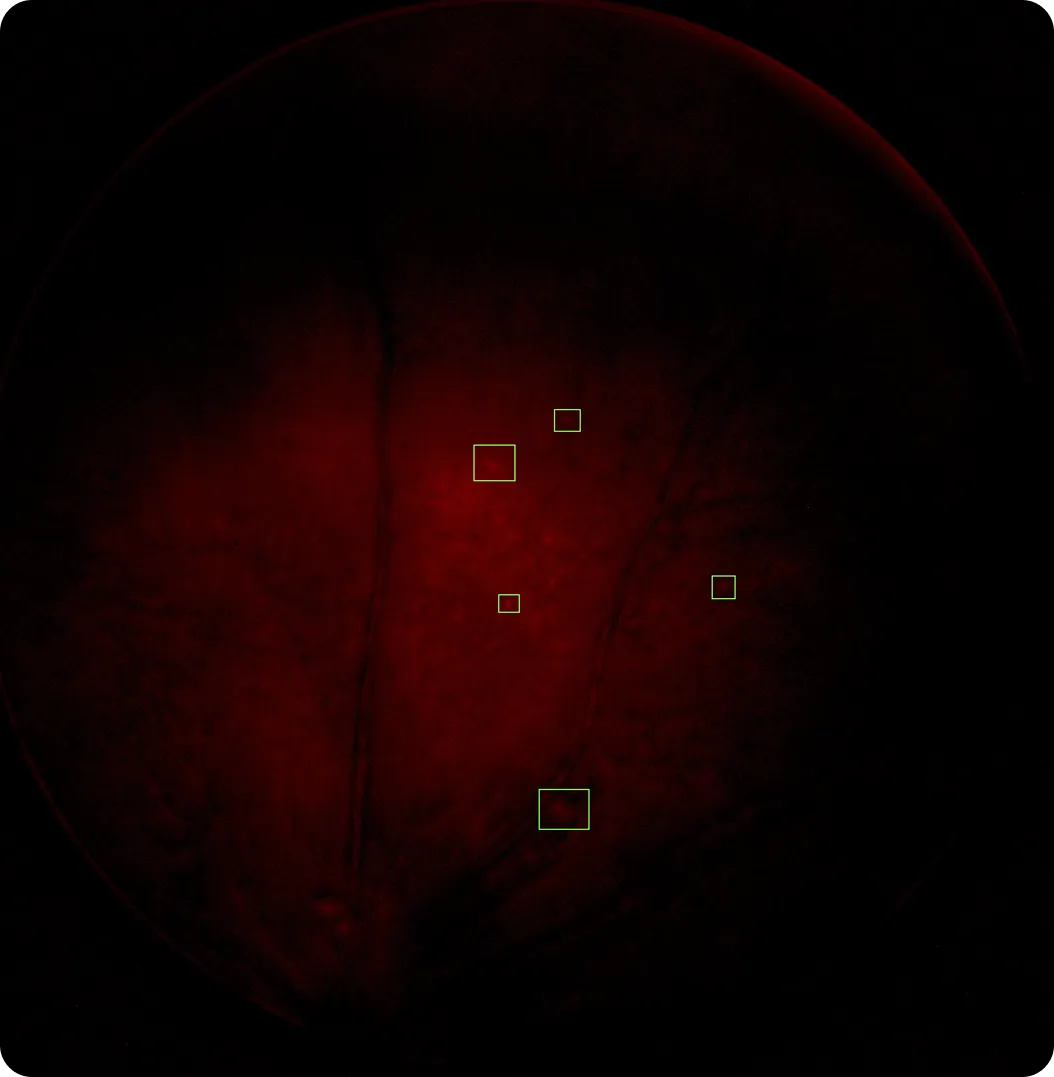

Bu yaklaşım, yakın zamanda CIBIR Alzheimer araştırma ekibiyle gerçekleştirilen bir işbirliği kapsamında uygulandı; bu işbirliği kapsamında Pixelabs, retina görüntülemeyi kullanarak farelerde Alzheimer hastalığının erken teşhisini destekleyen bir sistem geliştirdi. Amaç, hastalığın erken aşamalarına işaret edebilecek amiloid beta birikintileri gibi küçük göstergeleri tespit etmekti.

Bunu gerçekleştirmek için Pixelabs, veri depolama, görüntü işleme ve kullanıcı arayüzünü birbirine bağlayan bir iş akışı oluşturdu. Laboratuvara özel fundus görüntüleme cihazlarıyla çekilen retina görüntüleri, öncelikle Güvenli Dosya Aktarım Protokolü (SFTP) aracılığıyla aktarılır ve merkezi bir sistemde depolanır; böylece büyük veri kümelerinin yönetimi ve erişimi kolaylaştırılır.

Tutarlı sonuçlar elde etmek için, görüntü kalitesi ve aydınlatma farklılıklarını gidermek üzere ön işleme adımları uygulanır. Bu, sistemin farklı örnekler ve koşullar arasında doğruluğunu korumasına yardımcı olur.

Görüntüler daha sonra özel olarak eğitilmiş Ultralytics YOLOv8 modelleri dahil olmak üzere görsel AI modelleri kullanılarak analiz edilir. Performans ve doğruluk arasında denge sağlamak için YOLOv8 orta ve büyük varyantları YOLOv8 .

Bu süreçte, Ultralytics YOLO , amiloid beta birikintileri gibi küçük ilgi alanlarını doğrudan retina görüntülerinde tespit etmek ve konumlarını belirlemek amacıyla nesne algılama ve görüntü sınıflandırması için kullanılmaktadır.

Son olarak, sonuçlar web tabanlı bir platform üzerinden sunulur; burada kullanıcılar görüntü yükleyebilir, verileri yaş, cinsiyet veya fenotip gibi özelliklere göre filtreleyebilir ve tespit edilen özellikleri güvenlilik puanlarıyla birlikte görüntüleyebilir. Bu sayede, ham görüntü verilerinden net ve kullanışlı içgörülere ulaşmak daha kolay hale gelir.

Ultralytics YOLO Pixelabs AI-Engine'e entegrasyonu, analiz performansında belirgin bir iyileşme sağladı. Alzheimer araştırması kullanım örneğinde, sistem yaklaşık %90'lık bir hatırlama oranı elde etti; hastalık ilerledikçe ve belirtiler daha belirgin hale geldikçe bu oran %95'e kadar yükseldi.

Bu, araştırmacıların geniş görüntü veri kümeleri üzerinde amiloid beta birikintileri gibi detect özellikleri daha güvenilir bir şekilde detect etmelerine olanak sağladı. Sonuç olarak, analiz daha tutarlı hale geldi; bu da değişkenliği azalttı ve önemli göstergelerin gözden kaçmamasını sağladı.